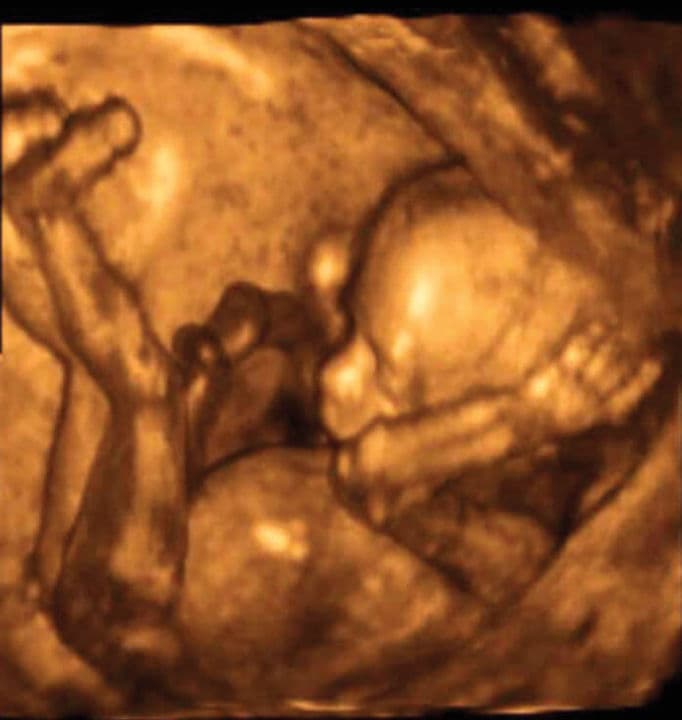

You will probably not be able to feel your baby move yet, but he is incredibly active inside your uterus. Somersaults and stretches are part of his daily routine, as are thumb and toe sucking. Your baby moves when awake and asleep: he has no control over his movements at this stage. Ultrasound scans reveal a huge range of movement in between inactive periods.